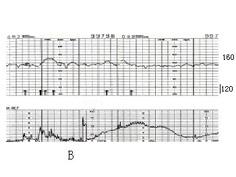

问题 如图A、B、C、D描记的胎心率种类正确的一项 ( )

选项 A、正常胎心率,NST反应型,晚期减速,早期减速 B、基线静止型,NST反应型,变异减速,晚期减速 C、基线静止型,NST反应型,晚期减速,早期减速 D、心动过速,NST无反应型,晚期减速,早期减速 E、正常胎心率,NST反应型,变异减速,早期减速

答案 C